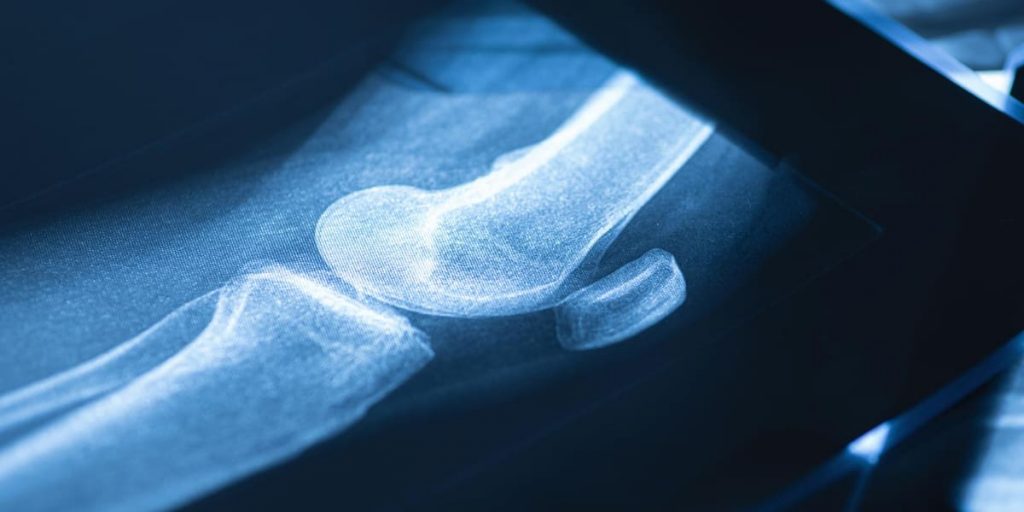

Radang sendi atau yang lebih umum disebut dengan arthritis merupakan peradangan atau pembengkakan yang membuat sendiri menjadi kaku sehingga sulit untuk digerakan.

Radang sendi mempunyai banyak jenis radang yang dapat diketahui, namun yang paling umum terjadi adalah rheumatoid arthritis atau rematik dan osteoarthritis.

Osteoarthritis merupakan penyakit sendi degeneratif yang disebabkan karena habisnya tulang rawan, menyerang orang berusia lanjut atau setelah 50 tahun.

Osteoarthritis disebut sebagai radang sendi yang sering disebabkan oleh penipisan dan kerusakan tulang rawan. Penyakit ini menyebabkan gesekan langsung antartulang.